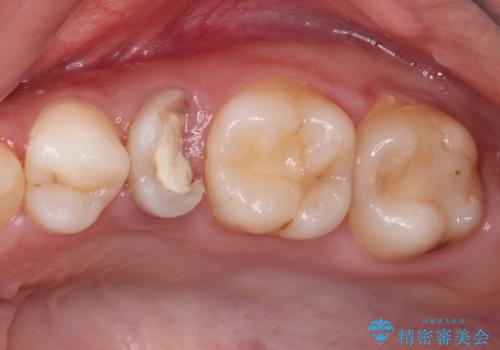

抜歯と言われた奥歯 根管治療と補綴治療